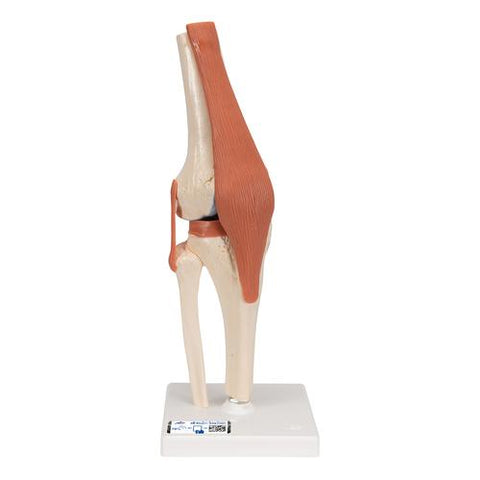

Functional Human Knee Joint Model with Ligaments & Marked Cartilage - 3B Smart Anatomy

This high-quality deluxe functional knee joint model with ligaments shows the anatomy and possible physiological movements of the human knee joint in exceptional detail. This model clearly demonstrates abductions, anteversion, retroversion, internal and external rotation. This knee joint model also clearly defines the ACL and PCL. The color of the natural-cast bones of the knee joint is extremely realistic. The cartilage on the knee joint surfaces is marked blue. This model consists of portions of the femur, tibia and fibula, menisci and patella. The Functional Knee joint model is mounted on a base for easy display.